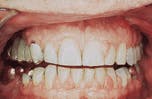

Case 3

Drug-related gingival hyperplasia

1. Identify the drug that is not a cause of drug-related gingival hyperplasia.

e. phenergan

2. Identify the major predisposing factor for drug-related gingival hyperplasia.

e. none of the above

3. Identify the best method to diagnose drug-related gingival hyperplasia.

4. Identify the true statement concerning drug-related gingival hyperplasia.

CASE 3: 1 = e; 2 = c; 3 = a; 4 = b